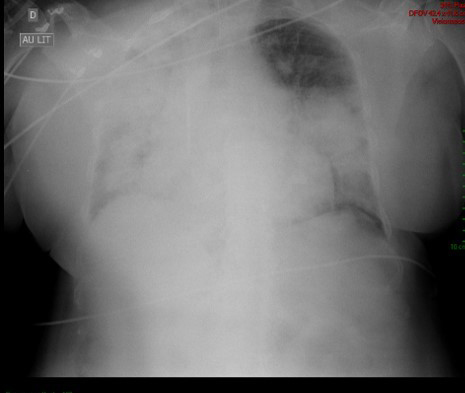

Vous confirmez la présence d’une protéinurie à 2,8 g/24 h. L’infirmière vous appelle car elle a constaté la présence de sang dans la sonde d’intubation. Un scanner thoracique est réalisé (figures 2a et 2b) :

Figure 2a (source : É. Crickx)

Figure 2b (source : É. Crickx)

Question 7 - Parmi les propositions suivantes, laquelle (ou lesquelles) est (sont) exacte(s) ?

Le scanner montre la présence d’opacités alvéolaires floues, confluentes et prédominant en périhilaire, tout en épargnant les régions sous-pleurales. Cet aspect est évocateur d’hémorragie intra-alvéolaire.